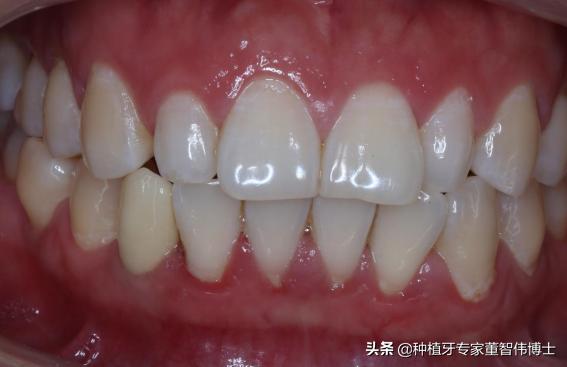

口内照-术后6月